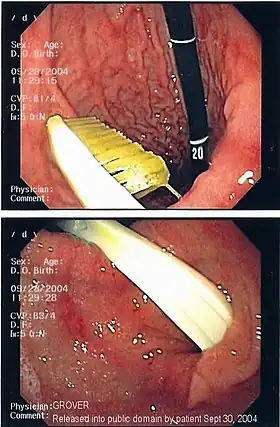

| A foreign body - in this case a swallowed toothbrush - located in the stomach cavity by using an endoscope. | |